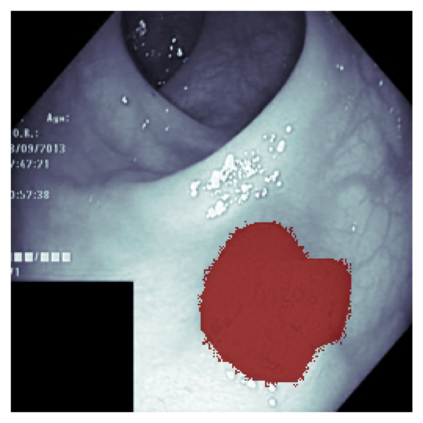

The sigmoid activation is the standard output activation function in binary classification and segmentation with neural networks. Still, there exist a variety of other potential output activation functions, which may lead to improved results in medical image segmentation. In this work, we consider how the asymptotic behavior of different output activation and loss functions affects the prediction probabilities and the corresponding segmentation errors. For cross entropy, we show that a faster rate of change of the activation function correlates with better predictions, while a slower rate of change can improve the calibration of probabilities. For dice loss, we found that the arctangent activation function is superior to the sigmoid function. Furthermore, we provide a test space for arbitrary output activation functions in the area of medical image segmentation. We tested seven activation functions in combination with three loss functions on four different medical image segmentation tasks to provide a classification of which function is best suited in this application scenario.